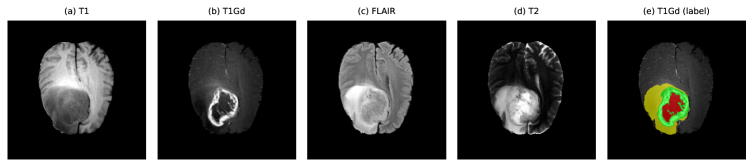

Refer to caption

Figure 1: All four channels of a sample BraTS-GLI patient and the corresponding manual segmentation overlaid on the T1Gd image. From left to right: T1, T1Gd, FLAIR, T2, and T1Gd with label map (red = NCR/NET, yellow = ED, green = ET). Figure created by Anthony Joon Hur using Python.

I use the BraTS 2023 Adult Glioma (GLI) Task 1 dataset, which builds on the BraTS benchmark series and the underlying TCGA-GBM and TCGA-LGG collections [2, 12, 8, 9, 10]. Each case consists of four co-registered MRI modalities (T1, T1Gd/T1c, T2, FLAIR) at 11 mm3 resolution and a segmentation mask with labels {0,1,2,4}\{0,1,2,4\} for background, necrotic or non-enhancing tumor, edema, and enhancing tumor, respectively. Figure 1 illustrates one example BraTS-GLI case and highlights the visual differences between modalities and the corresponding label map.